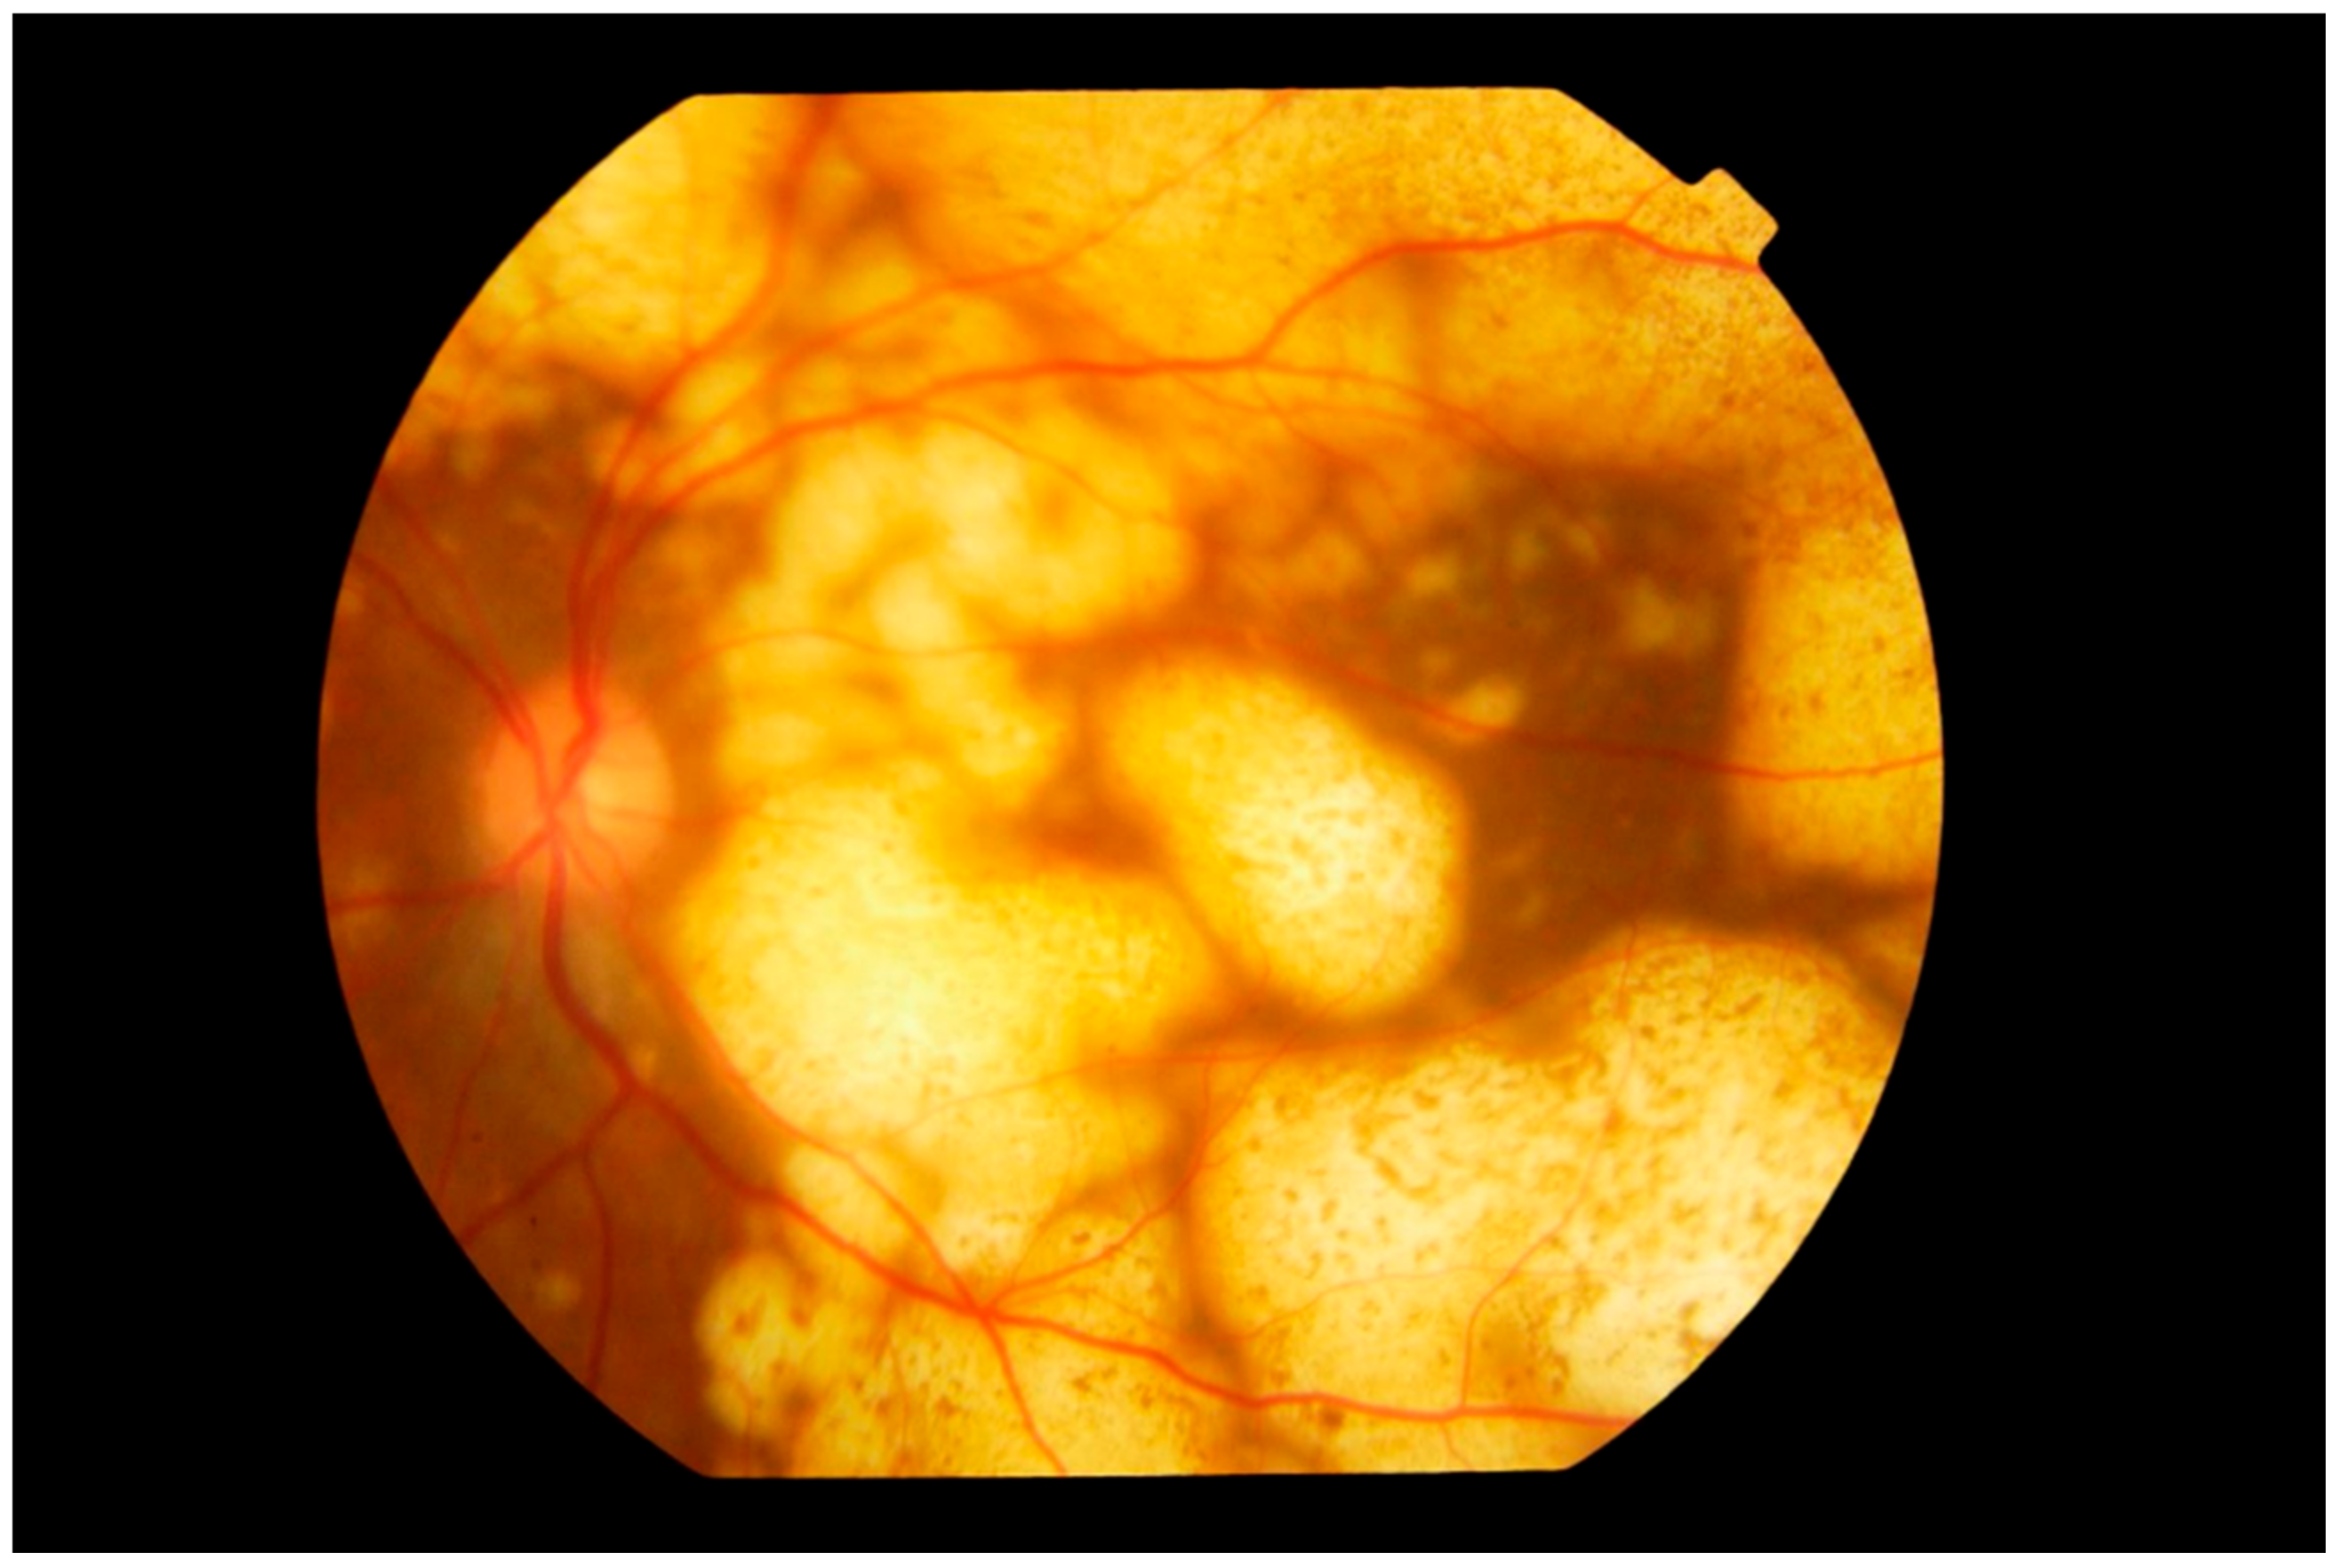

3. Clinical Features

4.1. Imaging

4.1.1. Fundus Autofluorescence

4.1.2. Spectral Domain Optical Coherence Tomography

4.1.3. Fluorescein Angiography

4.1.4. Indocyanine Green Angiography